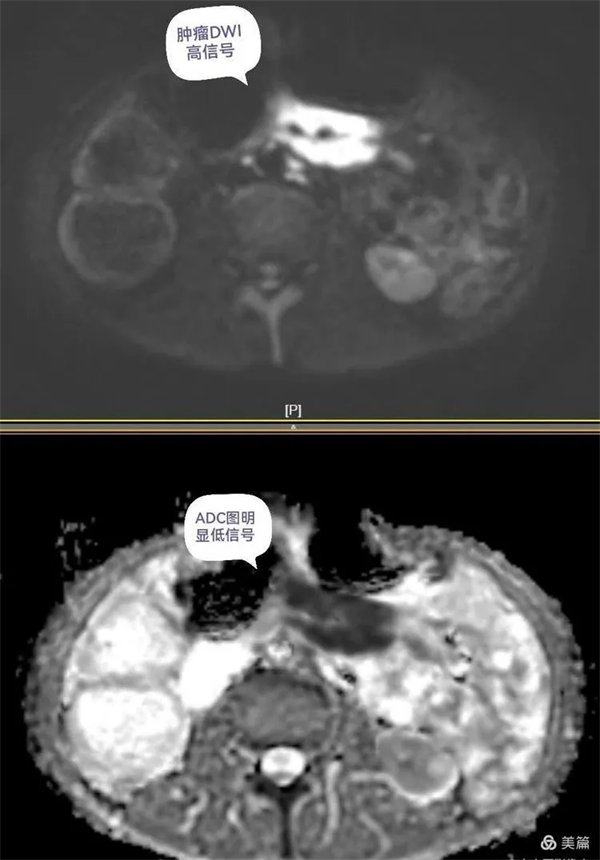

圖4:磁共振功能成像清晰顯示病變DWI呈明顯高信號,ADC圖呈低信號,腹膜后多發小結節灶。

圖5:DWI腫瘤呈明顯高信號,ADC圖呈低信號,中心為被包繞的腸系膜血管。